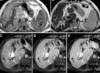

As lesões focais hepáticas na imagem são suspeitas para metástases.

Sequências GRE em fase/fora de fase.

A

Falso.

As lesões na imagem correspondem a esteatose multifocal/multinodular.